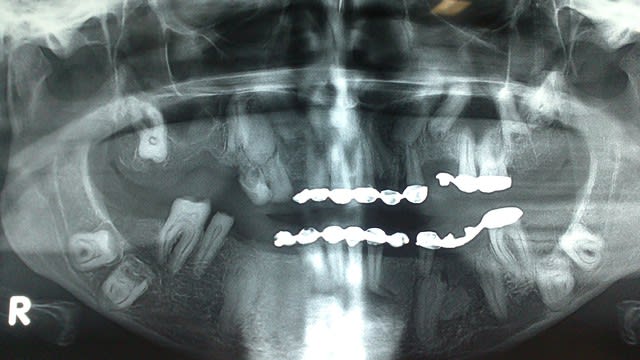

Bonjour, une jeune fille de 23 ans qui,selon son père,ne présente aucun problème de santé d'ordre général,à un retard d’éruption de plusieurs dents permanentes.

Un confrère lui à confectionner un bridge fixe sur des dents permanentes et lactéales mais la patiente ne peux pas manger à l'aise à cause des douleurs .

la forme des dents est bizarre, non???

cumulé avec le retard dentaire...y a pas un grand syndrome là dessous???

sinon, scan pour voir si les dents sont ankylosées (y a de fortes chances et là aussi çà joue en la faveur d'un syndrome...) dans un premier temps...histoire d'y voir plus clair...

Oui ça ressemble à une amélogénèse imparfaite

La pano parle d'elle-même, c'est plus qu'un simple retard d'éruption.